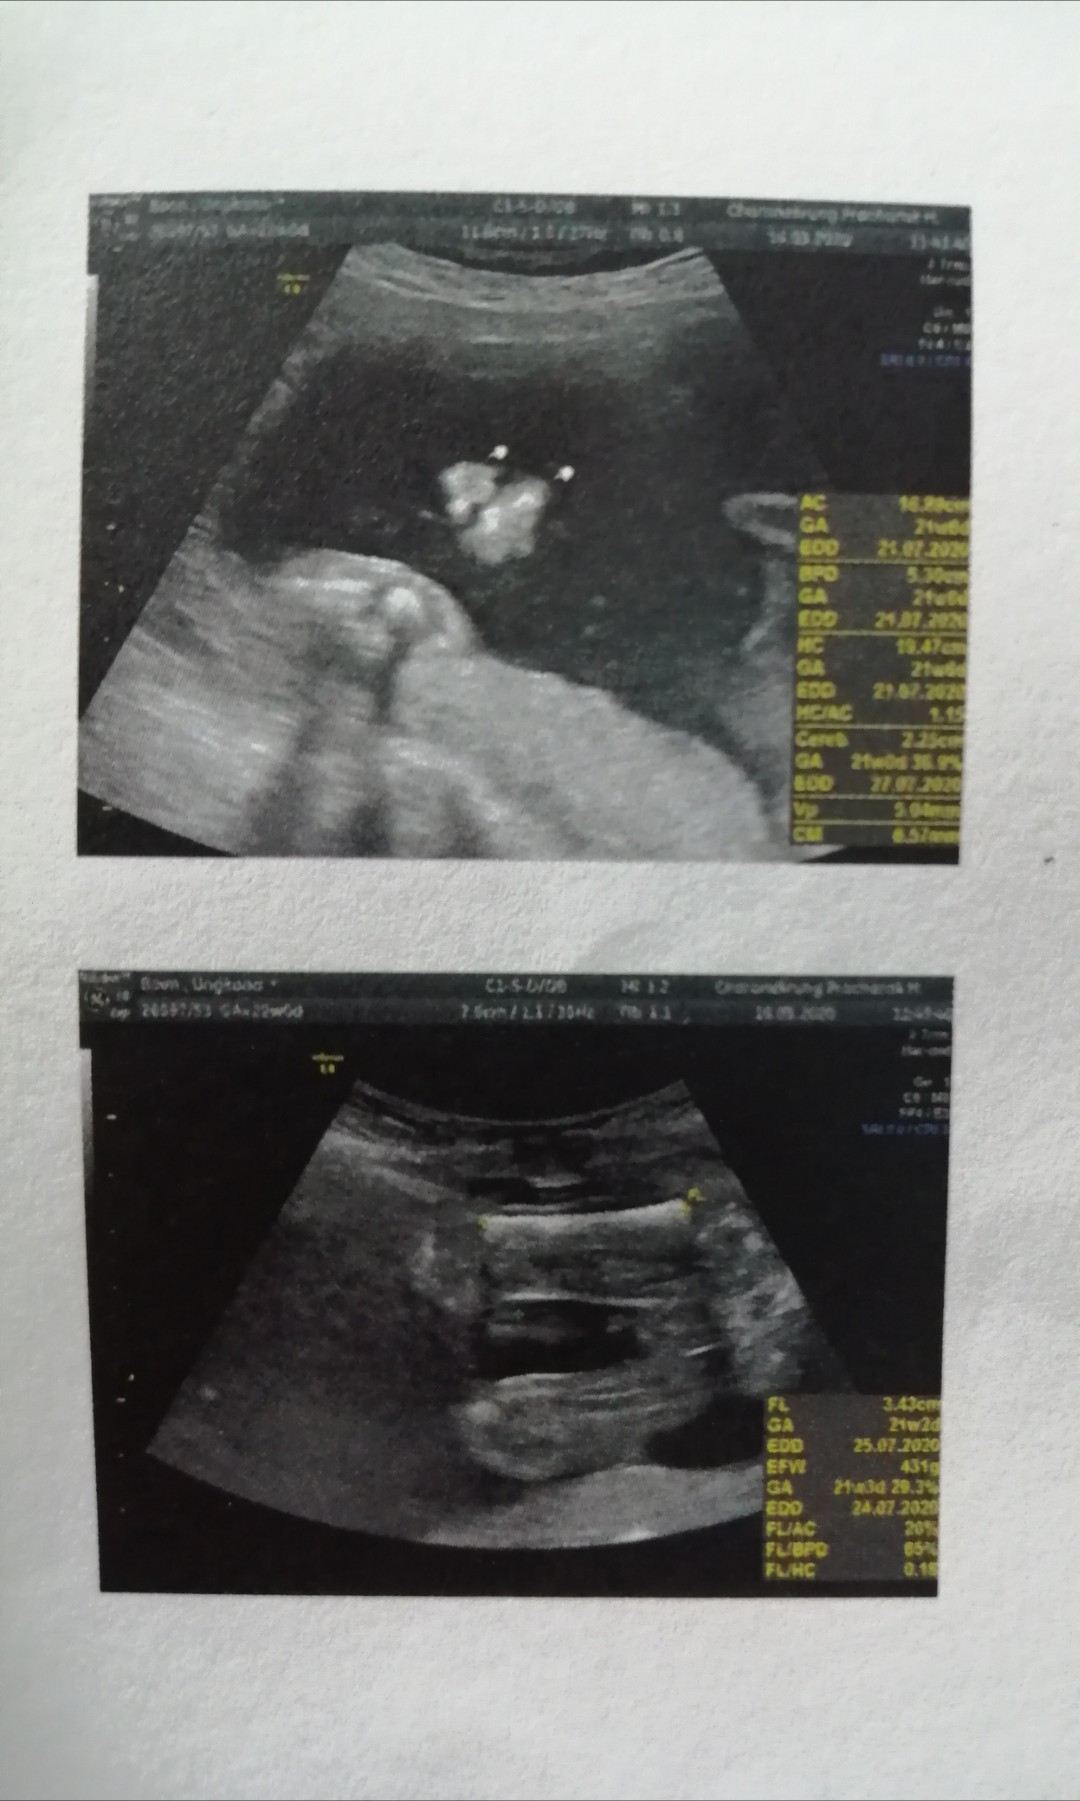

ใบอัลตร้าซาวด์

แม่ๆช่วยดูหน่อยคะ ผช.ใช่ไหมคะ หมอบอก ผช. บ้านไหนได้ ผช. ลงรูปใบซาวด์ให้ดูหน่อยคะ